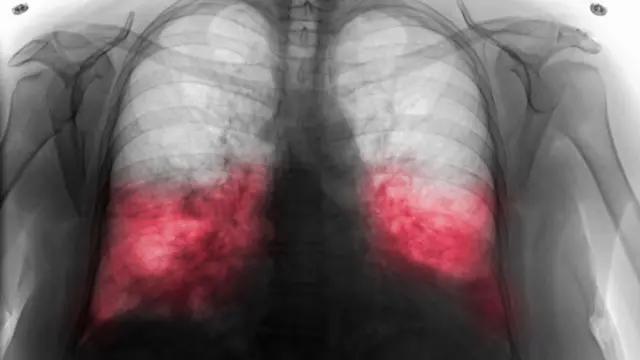

ఆయనకు సీటీ స్కాన్ చేయగా బైలేటరల్ న్యుమోనియా లక్షణాలు కనిపించాయని, అవి ప్రాథమిక దశలో ఉన్నాయని వాటికన్ సిటీ వర్గాలు వెల్లడించాయి.

న్యుమోనియా అంటే?

న్యుమోనియా ఒక ఇన్ఫెక్షన్. ఇది ఊపిరితిత్తుల్లో మంటను కలిగిస్తుంది. ఊపిరితిత్తుల్లోని గాలి సంచులు ద్రవాలతో నిండిపోయి కఫంతో కూడిన దగ్గు, చీము, జ్వరం, చలి, ఒళ్లు నొప్పులు, శ్వాస తీసుకోవడంలో ఇబ్బందులు వంటివి తలెత్తుతాయి.

బైలేటరల్ అంటే ఈ ఇన్ఫెక్షన్ ఒకటి కాకుండా రెండు ఊపిరితిత్తుల్లో కనిపిస్తుంది.